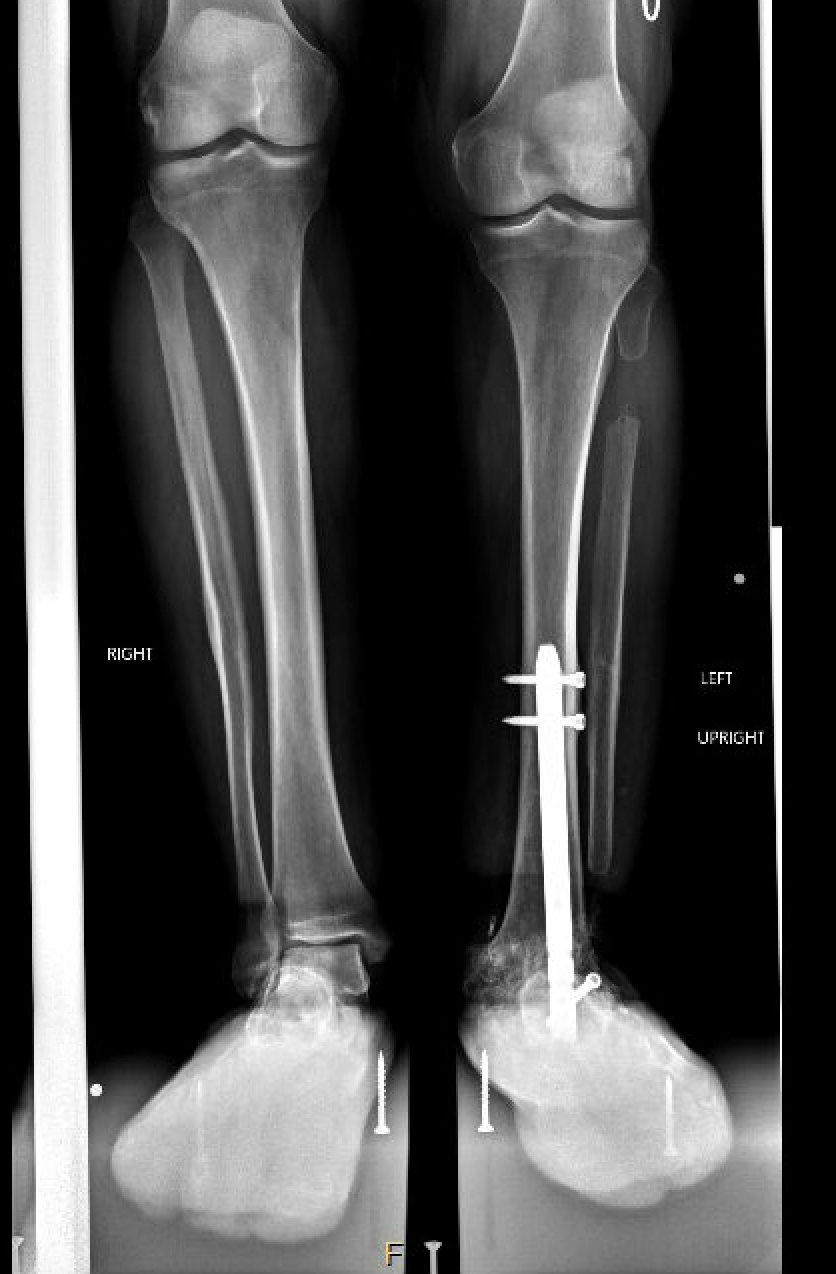

The operation took place in November 2022. Because Natale’s ankle was fused, Marecek chose to lengthen Natale’s tibia, or shin bone, rather than his femur. Marecek also identified that Natale’s ankle had been fused out of alignment. So, first he corrected the ankle’s alignment, then he broke Natale’s tibia and inserted a distraction rod—the kind that could push the two sides of the broken bone apart.

Natale could not put any weight on the leg for three months. After that the distraction rod was removed and replaced by a weight-bearing rod.

Natale says he had to do a lot of physical therapy, stretching the muscles to make space for the longer leg bone. It was about six months before Marecek gave him the go-ahead to put his full weight on it. Even after a year, X-rays showed the bone still hadn’t completely filled in the gap around the rod in his tibia.